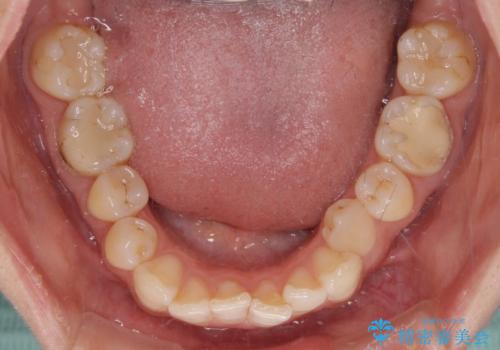

- 下顎の前歯が隠れていることと、デコボコを気にして来院された患者様です。

咬み合わせと目立っていた銀歯が改善され、患者様には大変満足していただきました。